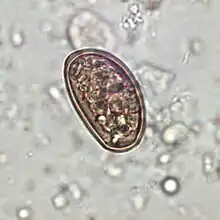

Dicrocoelium dendriticum egg in an unstained stool wet mount slide

Traditionally, diagnosis for dicrocoeliasis infection involves the identification of Dicrocoelium dendriticum eggs in the faeces of a human or other animal. However, in humans, eggs in the stool may be a result of ingesting raw infected animal liver and may not in fact indicate dicrocoeliasis.[9] Therefore, examining bile or duodenal fluid for eggs is a more accurate diagnostic technique in combination with a liver-free diet.[6]

In animals, diagnosis has traditionally involved stool examination or post-mortem examination of the liver. Recently, an ELISA using a Dicrocoelium dendriticum antigen was able to identify cases of dicrocoeliasis in sheep in Italy 28 days earlier than traditional methods.[11]